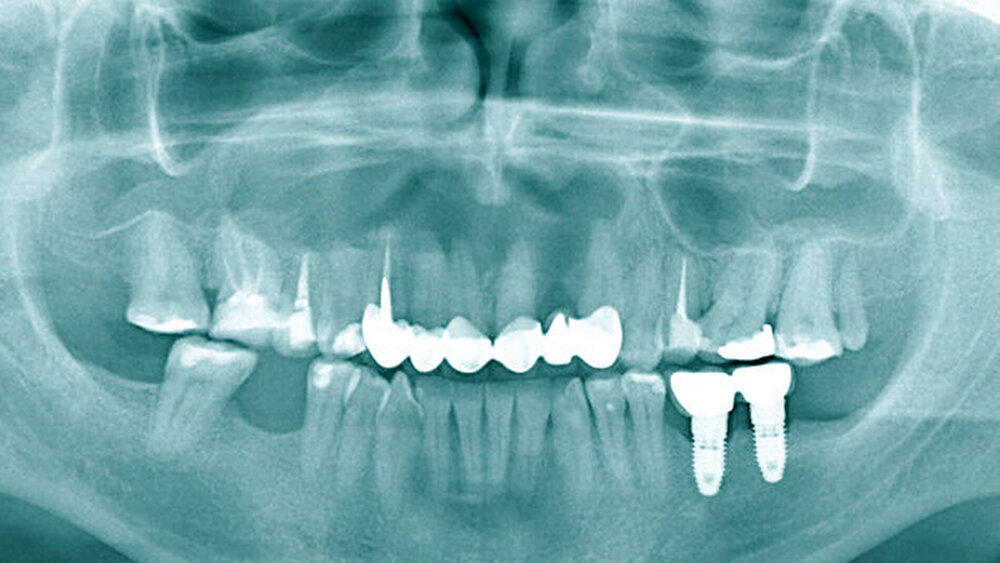

Eine 37-jährige Patientin stellte sich zur Weiterbehandlung einer radiologisch auffälligen Raumforderung im Bereich des Oberkiefers in unserer Ambulanz vor. Das vorhandene Orthopantomogramm (Abbildung 1) zeigte neben dem aktuellen Zahnstatus mit den bereits endodontisch behandelten Zähnen 16, 15, 13 und 25 sowie den implantologisch ersetzten Zähnen 36 und 37 eine zystische Raumforderung von regio 16 bis 23. Klinisch reagierten die Zähne 14, 12, 11, 21 und 23 auf Kälte sensibel. Es bestanden keine Zahnlockerungen. Vestibulär in regio 13 bis 15 stellte sich eine Knochenauftreibung mit auslösbarem, pergamentartigem Knistern dar. Zur dreidimensionalen Darstellung der Zyste wurde ein DVT des Oberkiefers erstellt (Abbildung 2).